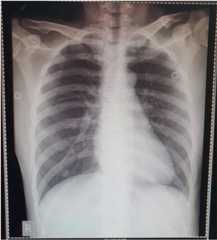

On illness day 12, he became increasingly dyspnoeic, hypoxic and agitated and was intubated and sedated with a midazolam drip. An endotracheal aspirate (ETA) and a further NPS/OPS were collected and sent to the RITM. Vancomycin, 30 mg/kg loading dose followed by 25 mg/kg BD, was commenced with a working diagnosis of severe community-acquired pneumonia due toStreptococcus pneumoniae secondary toInfluenza B infection, plus consideration of COVID-19 pending the ETA result. A complete blood count showed values within the normal range (Table1). On illness day 13, he continued to be febrile (38.5–40.0 °C) with bibasal crackles. Vital signs were stable with adequate urine output. A chest radiograph was reported as showing worsening of pneumonia (Fig.5).

Fig. 5.

Posteroanterior chest radiograph of patient 2, 30 January 2020 (illness day 13). Endotracheal tube in situ approximately 2 cm above the carina. There is worsening of the previously noted pneumonia